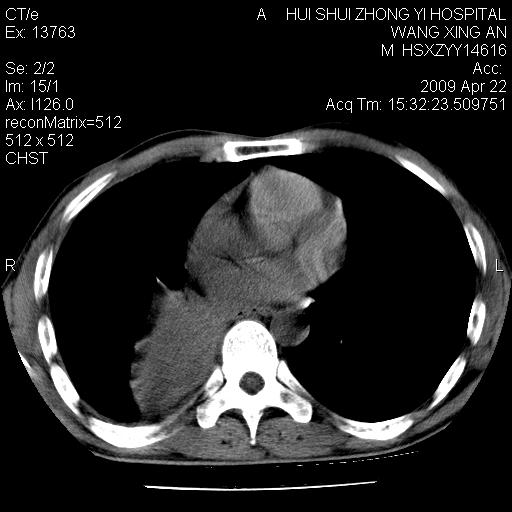

标题: CT19534:患者男、46岁咳嗽、胸痛半月。 [打印本页]

标题: CT19534:患者男、46岁咳嗽、胸痛半月。

考虑---右肺中心型肺癌继发下叶不张,少量胸水。

支持右侧中央型肺ca并右下肺不张、右侧胸腔少量积液。

1、右下肺中央型肺癌并右肺转移,右肺下叶不张。(右肺有结节影)。

2、右中上肺陈旧性肺结核(因为大多为纤维灶)。

3、右侧胸腔积液。

1、右下肺中央型肺癌并右肺转移,右肺下叶不张。(肿块围绕右肺下叶支气管生长,致管腔闭塞右肺下叶不张;右肺有结节影)。

2、右侧胸腔积液。

3、右中上肺陈旧性肺结核(右肺见纤维化病灶及点状钙化)。

1、右下肺中央型肺癌并右肺转移,右肺中下叶不张。(右肺有结节影)。胸骨转移

1)右肺中间段支气管癌并右肺下叶肺不张。2)右肺上叶、两肺下叶背段感染性病变。3)右侧少量胸腔积液。